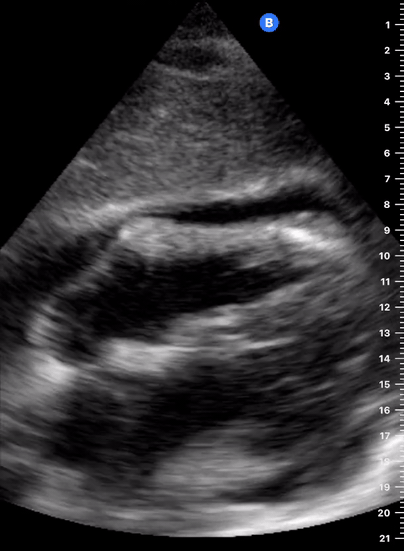

Depiction of E-point septal separation: M-mode is used to measure the distance between the open mitral valve and the ventricular septum. Measurements greater than 7 mm are suggestive of depressed systolic ejection. (1. RV free wall, 2. Interventricular septum, 3. Mitral valve, 4. LV free wall). From: The "5Es" of emergency physician-performed focused cardiac ultrasound (11).